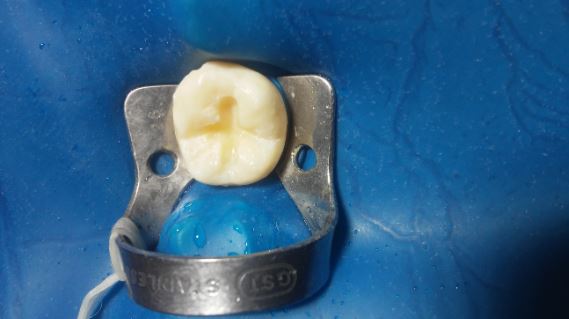

Caso clínico